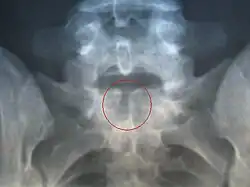

La espina bífida es una malformación congénita en la que existe un cierre incompleto del tubo neural al final del primer mes de vida embrionaria y posteriormente, el cierre incompleto de las últimas vértebras.

Básicamente existen dos tipos de espina bífida: la espina bífida oculta y la espina bífida abierta o quística.

Espina bífida oculta

Aparece un pequeño defecto o abertura en una o más vértebras. Algunas tienen un lipoma, hoyuelo, vellosidad localizada, mancha oscura o una protuberancia sobre la zona afectada. La médula espinal y los nervios no están alterados.